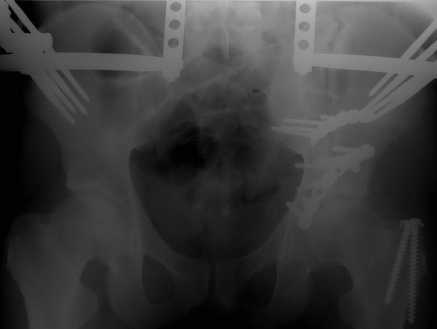

Добрый вечер, уважаемые коллеги. Прошу прощение за долгое молчание( компьютер был в долгосрочном ремонте). Больного с 9-ти месячной травмой таза мы прооперировали. Оценив свои возможности и совместив с вашими рекомендациями и советами (большое спасибо Рункову!), пошли задне-наружным доступом, с отсечением большого вертела. Закрепились 2-мя пластинками. Сверху закрепили аппаратом( передней рамой). На область перелома самого гребня повздошной кости не вмешивались. Снимки высылаю. Жду ваших отзывов и комментариев. Всем большое спасибо за активное участие в лечении больного. С ув.Андрей

Для чего аппарат? Или вы не уверены в стабильности вашей внутренней фиксации? Выглядит достаточно стабильно, аппарат позволит всего лишь чуть ранше дать нагрузку, и всё?

Внутренняя фиксация получилась достаточно стабильная.А передняя рама наложена с целью дополнительной фиксации для нейтрализации мышц прикрепляющихся к крылу подвздошной кости, и исключить возможное расшатывание и возникнование нестабильности внутрених фиксаторов( уж очень большая нагрузка на эти 2 пластины).На открытом этапе операции мобилизовали только часть линии всего перелома( около 1/4 части начиная от свода и проксимально), а остальная часть находится в рубце и патологическая подвижность в ней есть хоть и не выражена) А о ранней нагрузке никто и не думал. А как на ваш взгляд, в какие сроки в такой ситуации разрешить полную нагрузку? Я считаю, что только при сращении перелома, подвержденные лучше бы КТ